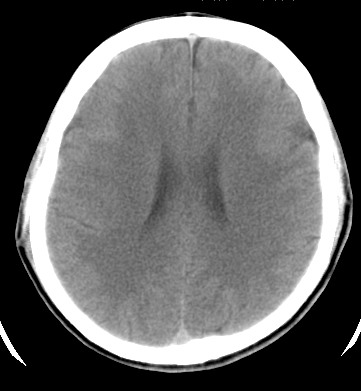

标题: CT17787:头ct,请帮忙看看右顶部有无异常 [打印本页]

标题: CT17787:头ct,请帮忙看看右顶部有无异常

男,58岁,偶有头疼

未见明显异常。右顶部低密度影为深入的脑沟。

增宽的脑沟!无异常!

是宽大的脑沟,局部不象有萎缩现象

增宽的脑沟

诊断依据:

低密度影周围脑组织边缘均有一层脑灰质覆盖。

正常啊,是对右顶增宽脑沟有疑问吗